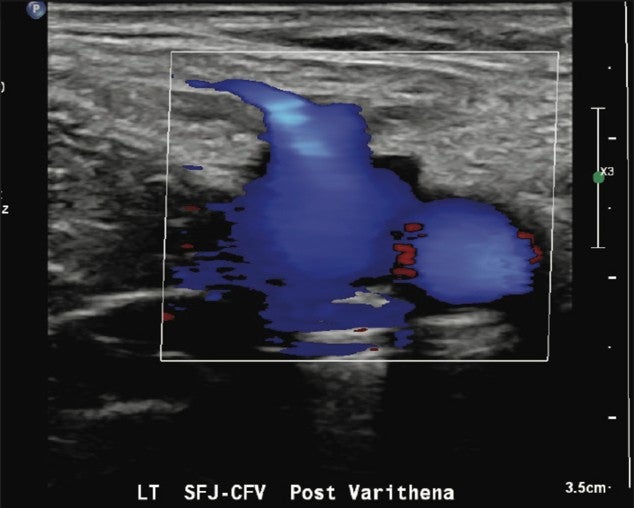

Immediately after the procedure, successful venospasm of the treated varicosities and residual GSV were documented with duplex and grayscale imaging. A final ultrasound image was obtained to confirm a patent and compressible left common femoral vein Saphenofemoral Junction (SFJ).

Figure 5. Color flow to confirm patency of left CFV/SFJ post Varithena treatment.